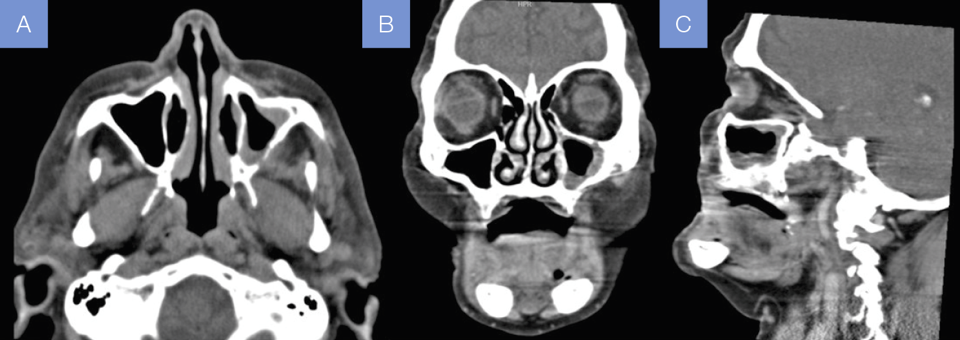

En

urgencias se solicitó una tomografía axial computarizada del macizo facial con

contraste (Fig. 1), la cual informa engrosamiento de la mucosa del seno maxilar

izquierdo con presencia de calcificaciones mucoperiósticas, esclerosis de sus

paredes y obliteración secundaria del complejo osteomeatal izquierdo.

Figura 1. Tomografía

axial computarizada preoperatoria con contraste, (A) con corte axial, (B) corte

coronal, (C) corte sagital.